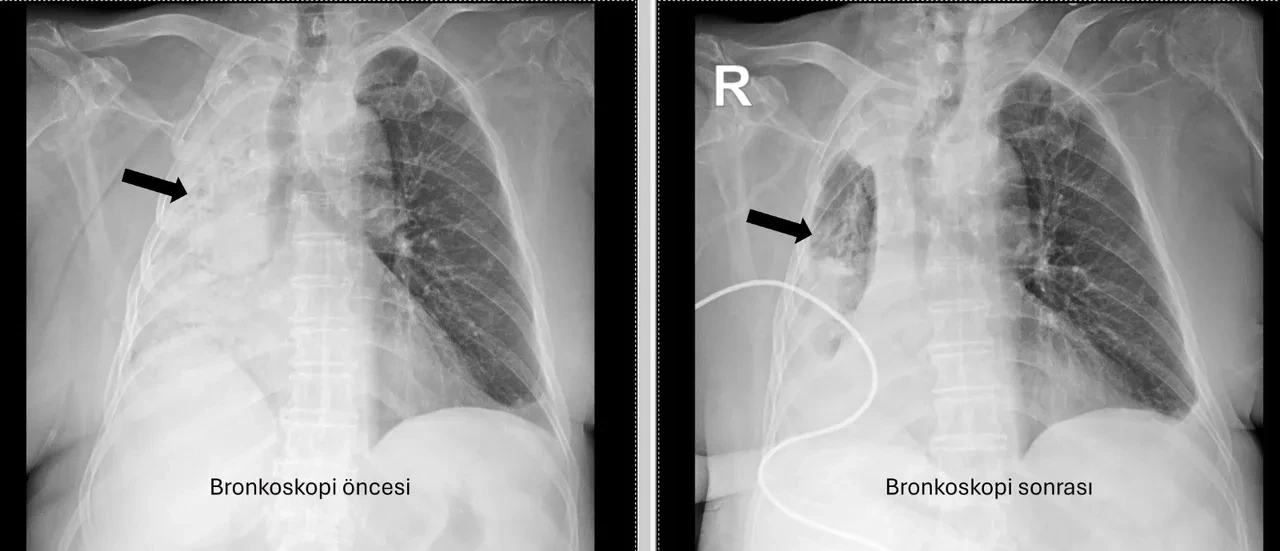

Göğüs Hastalıkları Anabilim Dalı Öğr. Üyesi Prof. Dr. Göksel Altınışık Ergur, tarafından yapılan tetkiklerde sağ akciğere giden hava yolunun bütünüyle kapalı olduğu görüldü. Hastaya acil bronkoskopi planlanıp hemen işlemin gerçekleştirildiğini söyleyen Prof. Dr. Altınışık Ergur, yapılan müdahaleyi şöyle anlattı:

"Fleksibl (esnek, eğilip bükülebilir) bronkoskop ile hava yolları incelenirken çok yoğun ve koyu sekresyon olduğu, bunun iyice temizlenmesi sonucunda ancak hava yollarının incelenebileceği görüldü. Aspiratör (içerideki salgıları emmeye yarayan bir cihaz) sayesinde hava yollarına steril sıvı verilip emilerek bu temizlik yapıldı. Sonrasında sağ akciğere giden hava yolunda sarı bir nesne olduğu görüldü. Bu hâliyle yabancı cisim olduğu anlaşıldığı gibi bunun mısır tanesine benzerliği de açıktı. Yabancı cismi çıkarma işlemi genel anestezi altında, rijit bronkoskop ile yapılmak üzere planlanabilirdi; çünkü bu durumun tedavisi yabancı cismin oradan, ek sorun oluşturmaksızın çıkarmaktı. Ancak, genel anestezi altındaki bir işlem için hastanın genel durumu bozuk olduğundan, özellikle ek hastalıkları ve enfeksiyon varlığı ile işlem riski artacağından hastadaki cismin fark edildiği sırada çıkarılmasına şans vermek daha uygun görüldü. Hava yolu içindeki sıvıları emen aspiratörün gücünü kullanılarak cismin çıkarılması mümkündü.

Bronkoskobun ucu, sarı cismin gövdesine dayanıp aspiratör ile emme sayesinde ikisi birbirine sımsıkı yapıştırıldı. Emme gücünün azaltılmamasına dikkat ederek yabancı cisim ve bronkoskop, aynı zamanda hava yollarından dışarıya başarı ile çıkarıldı. İşlem sonrasında hasta yakınına mısır tanesi açısından tıbbi öykü yeniden sorulduğunda, hastamızın bundan beş ay önce yediği pizzanın üzerinde mısır taneleri olduğu öğrenildi. O sırada ani bir yakınma ortaya çıkmadığı için böyle bir ihtimal akla gelmemişti. Düşkün hastalar taneli gıdalar yerken, bu durumun fark edilmeden de gelişebileceğini göstermesi açısından önemli olan bu tablo, hastaların bir dedektif titizliği ile değerlendirilmesi gerekliliğini bir kez daha ortaya koymaktadır."